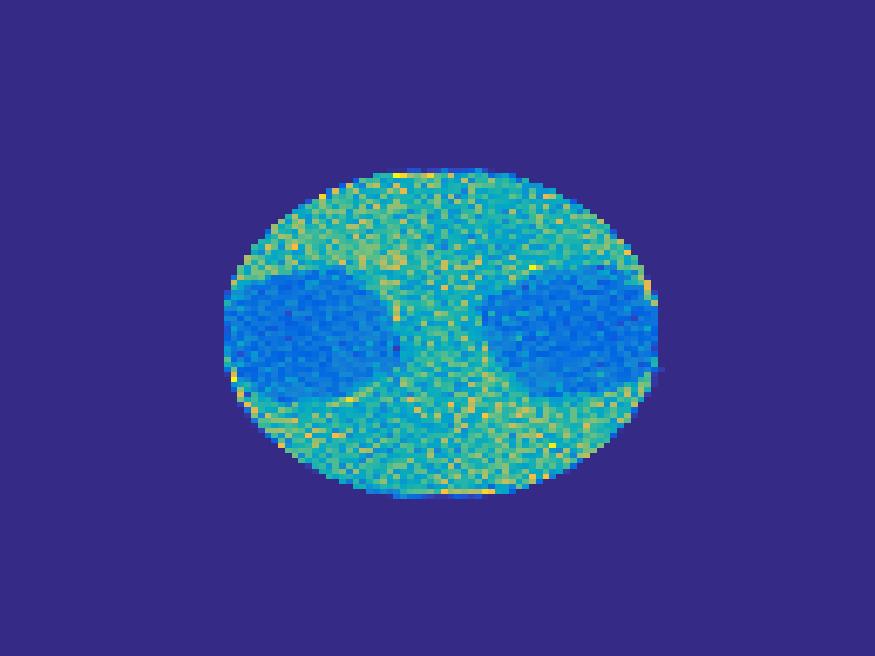

The proposed method is tested on numerical phantoms for a proof of concept study. We simulate image frames of size and projections per frame. Three time activity curves (TAC) for blood, liver and myocardium, previously used in [14] (see Figure 1), are used to simulate the dynamic images. The first simulated dynamic phantom is composed of two ellipses. In temporal direction, the positions of the two ellipses are stationary while the intensity in 90 frames within the region of each ellipse is generated according to the TAC of blood or liver. The projections are generated by using Radon transform sequentially performed for each frame.

In the tests, projections at two orthogonal angles are simulated for every frame to mimic 2-head camera data collection. The projection angles increase sequentially by along temporal direction. For example, at frame 1, projections are simulated at angle and , and at frame 2, angle and , etc. Finally, white Gaussian noise is added to the projection data. Reconstruction results with different methods are shown in Figure 3. Since the number of projections is very limited for each frame, the traditional FBP and least square methods cannot reconstruct the images satisfactorily, while the proposed method is capable to reconstruct the images effectively. Compared with SEMF model, when the edge of images jump (see frame 21 -frame 31 in Figure 3), the proposed model can better capture the change of the tendency of TAC.